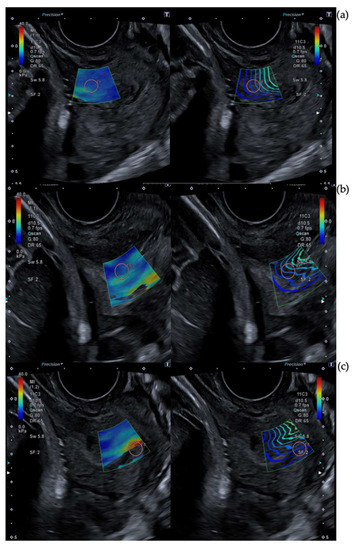

2.3. Cervical Shear Wave Elastography Measurement